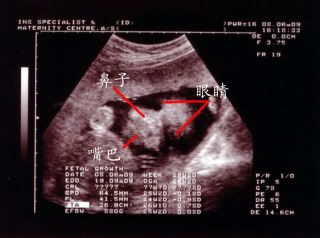

有那么明显吗?? 还看到宝宝的嘴巴像爸爸。。  |